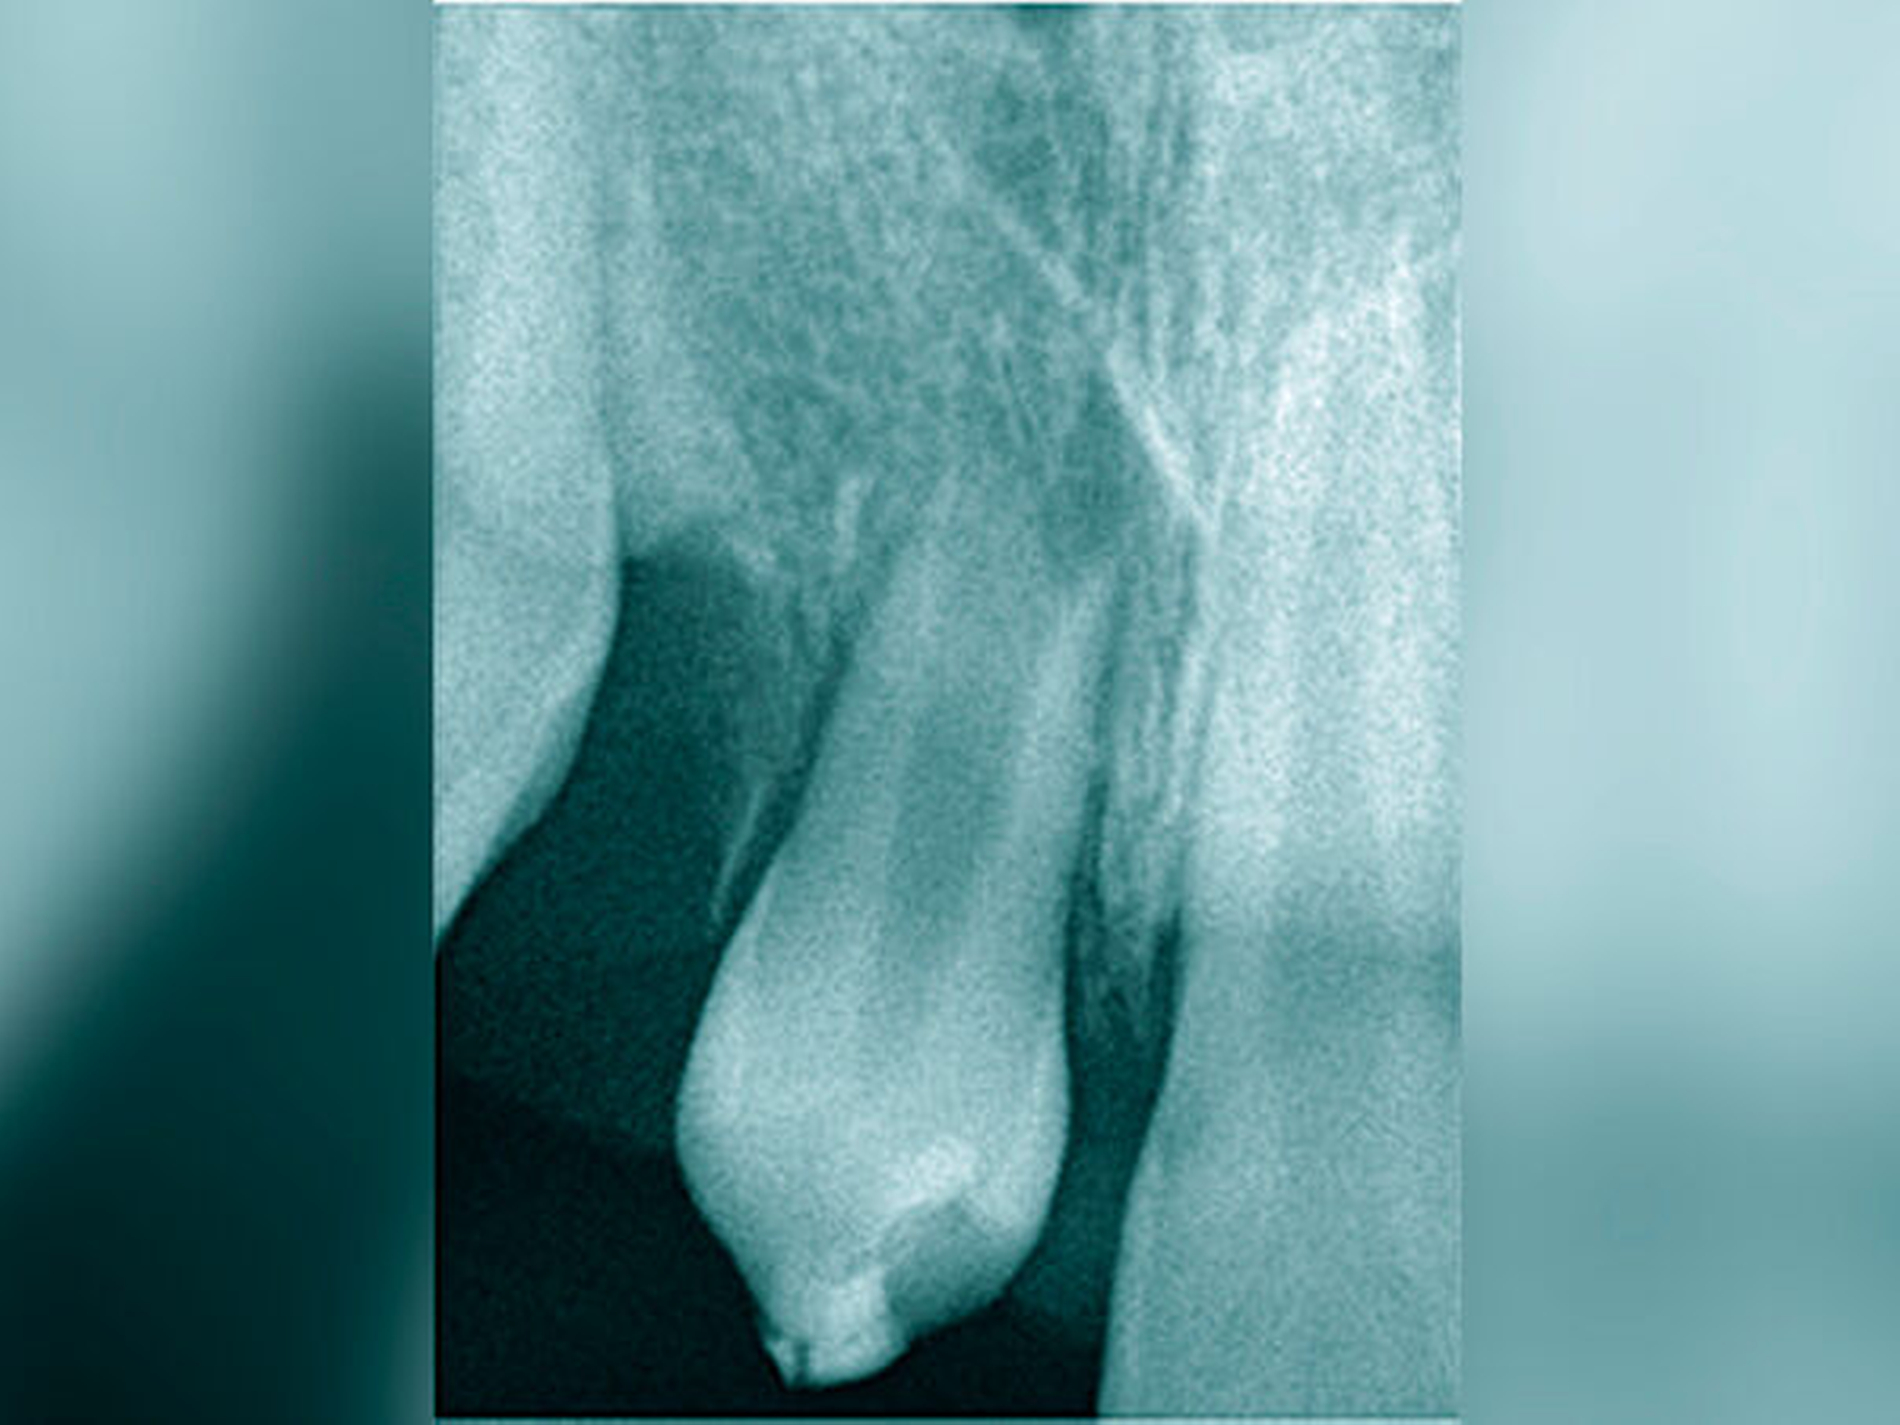

Das Wurzelwachstum des Transplantats sollte zum Zeitpunkt der Entnahme nicht mehr als zwei Drittel betragen. Dies kann eine operative Freilegung notwendig machen (Abb. 3).

Die große Regenerationspotenz des Zahnkeims, insbesondere während des Wurzelwachstums, ist Garant für deren Fortsetzung und den Erhalt der Vitalität in einer neu präparierten Alveole. Andreasen et al. [2007] bezeichnen die Neuformierung des Parodonts als den Schlüssel für eine erfolgreiche Transplantation. Zwei Drittel des Wurzelwachstums, ein offenes Foramen apicale (> 2 mm) und ein einwurzeliger Prämolar aus dem Unterkiefer gibt er als ideale Voraussetzungen für eine Erfolgsrate von 100 Prozent an. Eine weitere Voraussetzung ist die rasche Transplantation von der Spender- in die Empfängeralveole. Die Präparation der Schneidezahnalveole mit einem Dummy garantiert die optimale Passfähigkeit.